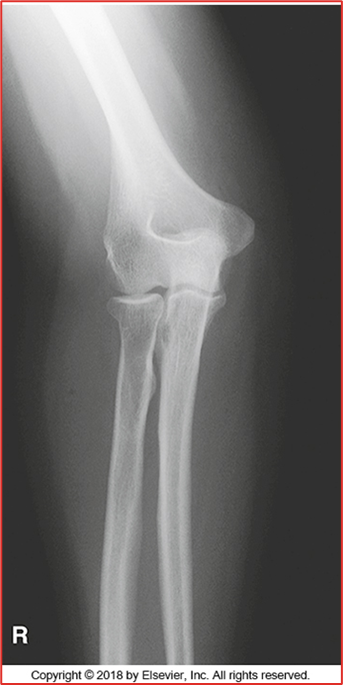

these 2 elbow images are in what position (2 for 1!!)

in this AP Partial Flexion is the humerus or forearm parallel

these 2 images of the elbow are in what position (2 for 1!) CR perpendicular to humerus and then CR perpendicular to forearm

this acute flexion of the elbow image is showing the __ __

what 2 position (2 images each) compromises for an AP elbow radiograph

-All anatomy present (humerus, radius, and ulna)

-Only should be partial superimposition of the radius and ulna (this image they are fully separated)

-They are laterally rotated (fix by medially rotating them and feeling the epicondyles)

-Epicondyles not perfectly in profile (due to rotation)

-Olecranon in olecranon fossa

-Open Joint Space = pretty good

-No crowning of radial head (good)

• REPEAT

Critique this AP Elbow Image